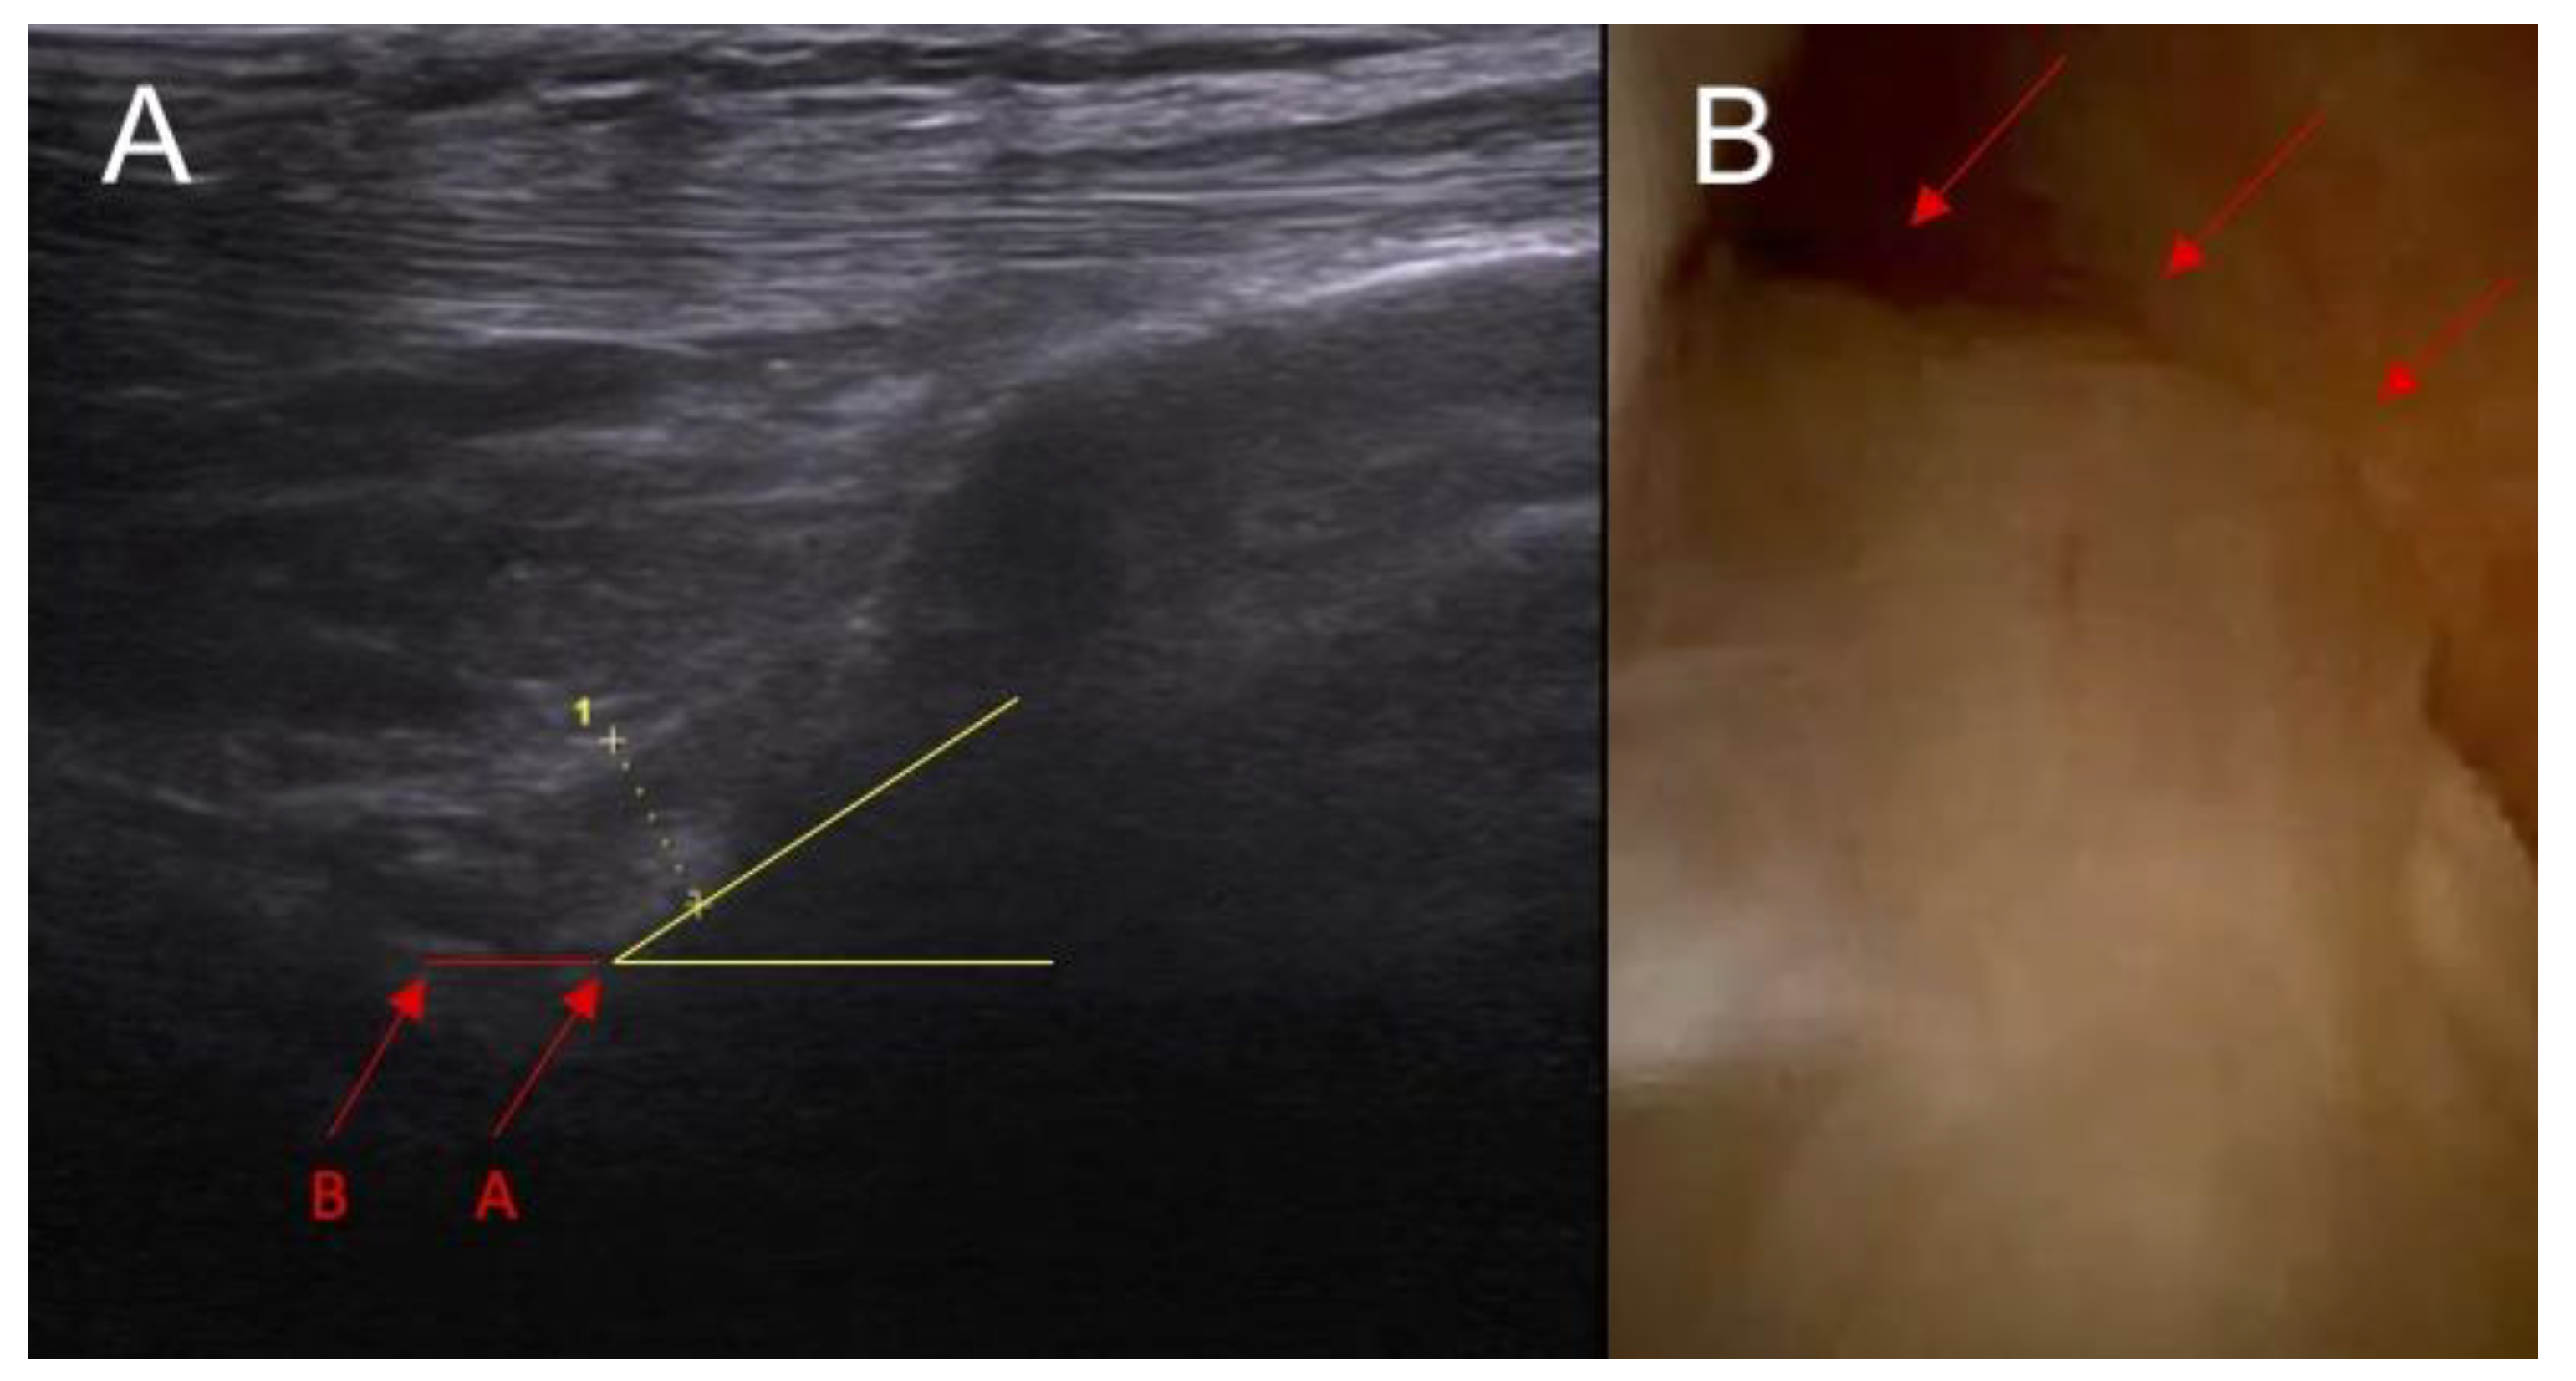

- The inclination of the ACL—patient is in supine position with a knee flexion of 90 degrees. The transducer is applied along the sagittal plane parallel to the longitudinal axis of patellar ligament. Inclination angle is the angle between base line and front line of the ACL.

- Swelling/scarifications of the ACL proximal attached to lateral femoral condyle—the patient is in prone position with knee full extension. The transducer is applied transversely to long axis of the lower limb in popliteal fossa.

2.1. Part I—Anatomical Study

3.1. Part I—Anatomical Study